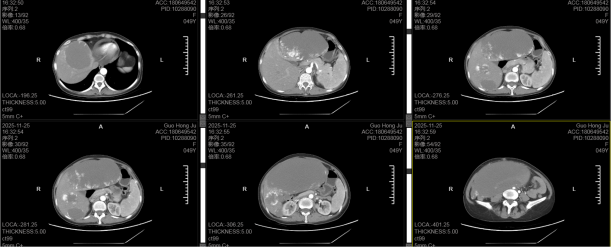

50岁女性患者因腹部胀痛在我院肝胆胰外科门诊就医时,腹部CT影像结果显示患者腹腔被一个肝脏巨型血管瘤撑满,直径大小约30×25厘米,肝脏巨大肿瘤已压迫下腔静脉、门静脉等关键血管,稍有外力就可能破裂引发大出血。更棘手的是,长期瘤体消耗及腹腔胃肠道受压迫导致食欲差、长期营养摄入不足等,让患者的血红蛋白仅69g/L(正常女性约120-150g/L),中度贫血的身体根本扛不住常规手术;而血库同型血储备不足,手术出血风险激增。

术前腹部CT

手术切除是唯一根治方案,但30×25厘米的肿瘤体积、15公斤的重量,加上患者术前中度贫血,让手术难度陡增。既要完整剥离与肝脏血管、胆管紧密粘连的肿瘤,又要避免损伤正常肝组织,更要解决术中血液丢失过多的棘手问题。